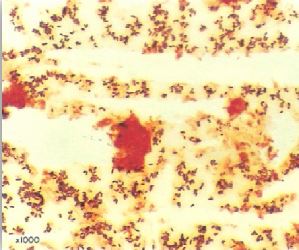

محامي وصل منذ ثلاثة أيام من السفر أحضر إلى قسم الطوارئ وهو يعاني من تقرح الحلق sore throat و orodynia ، صداع مع فشل عام، كما يعاني من ارتفاع في درجة الحرارة ونوبات تسرع ضربات القلم tachycardia . بفحص البلعوم لوحظ وجود غشاء ملتصق على الحلقوم. اخذت مسحة وأرسلت إلى مختبر التحليل الجرثومي لفحصها مجهرياً كما في الشكل رقم 1 وزراعتها على وسط غذائي مناسب كما في الشكل رقم 2 . تم إجراء الاختبار المعملي كما في الشكل رقم 3 .

الشكل رقم 1 : الفحص المجهري

2- يتم التاكد من التشخيص بأخذ مسحة من الحلق والأنف لفحصها مجهرياً وزراعتها على الوسط الغذائي المناسب وهو الوسط الغذائي Hoyle's أو الوسط الغذائي Tindsale's medium وهما وسط غذائي انتقائي وتفريقي.

وكذلك الوسط الغذائي المغذي Loeffler's agar المائل ويتم التعرف على البكتيريا المعزولة بإجراء الاختبارات الكيموحيوية ويكشف على الذيفان بطريقة Elek's كما في الشكل رقم 3 ، حيث يجري هذا الاختبار بغمر ورقة الترشيح في مضاد الذيفان ثم وضعها على الطبق المحتوي على الوسط الغذائي المناسب ، بعد ذلك تزرع البكتيريا قيد الاختبار على الطبق مع زرع بكتيريا سالبة وأخرى موجبة لهذا الاختبار على الطبق مع زرع بكتيريا سالبة وأخرى موجبة لهذا الاختبار للتأكد من صحة النتائج المتحصل عليها، إلا أنه من الأفضل استعمال تقنية التفاعل التسلسلي للبوليمرات (PCR) للكشف عن السلالات المنتجة للذيفان.